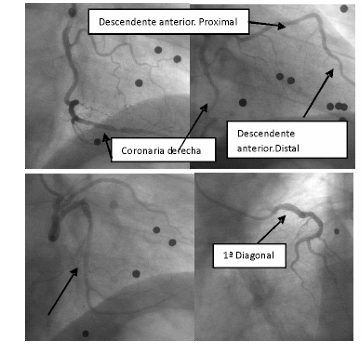

Anomalía congénita de la arteria coronaria izquierda

IMÁGENES EN CARDIOLOGÍA